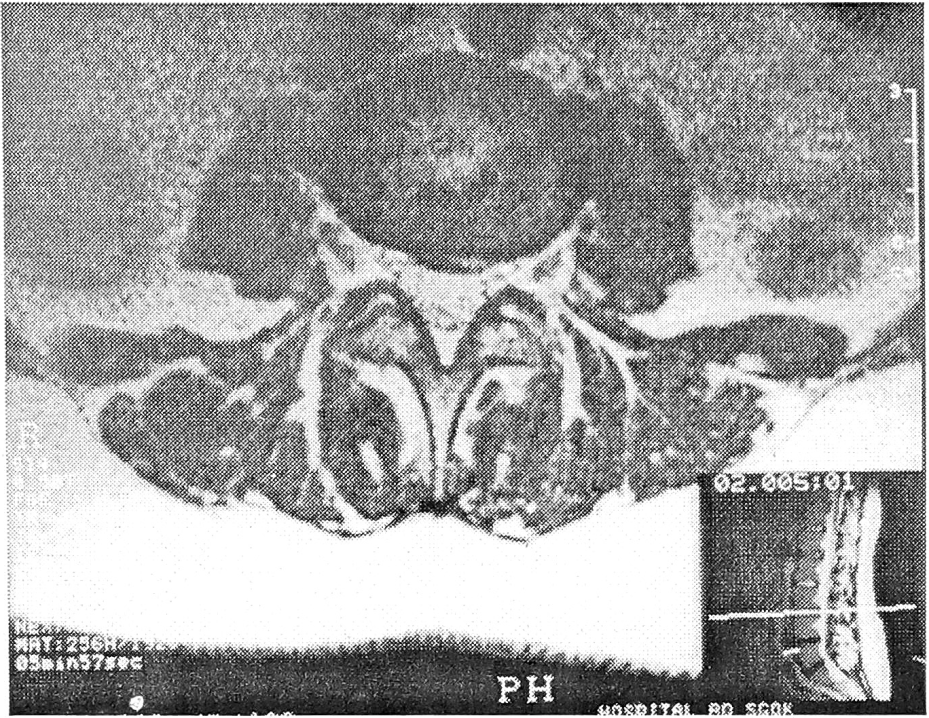

При внутридисковых перемещениях студенистого ядра определялось незначительное увеличение емкости диска, которая составляла 1,0 (±0,2—0,3) мл. Введение контрастного вещества в диск провоцировало поясничную боль средней интенсивности. Нуклеарная тень занимала не менее половины диаметра диска и выглядела фрагментированной, с наличием трещин, идущих от центральной тени к периферии диска (см. рис. 1).

Рис. 1. Внутридисковые перемещения студенистого ядра L3—4 диска.

Протрузии нижних замыкательных пластинок L4, L5 позвонков.

Протрузии замыкательных пластинок — один из специфических дискографических признаков поясничной остеохондропатии, характеризующейся незначительной дегенерацией студенистого ядра. Выступающий фрагмент последнего вплотную прилегал к вдавленной им в тело позвонка замыкательной пластинке, не проникая за ее пределы (см. рис. 1 и 6). В 5 случаях отмечалось контрастирование прилежащего участка замыкательной пластинки. Емкость диска не превышала 1 мл; его инъецирование было безболезненным.